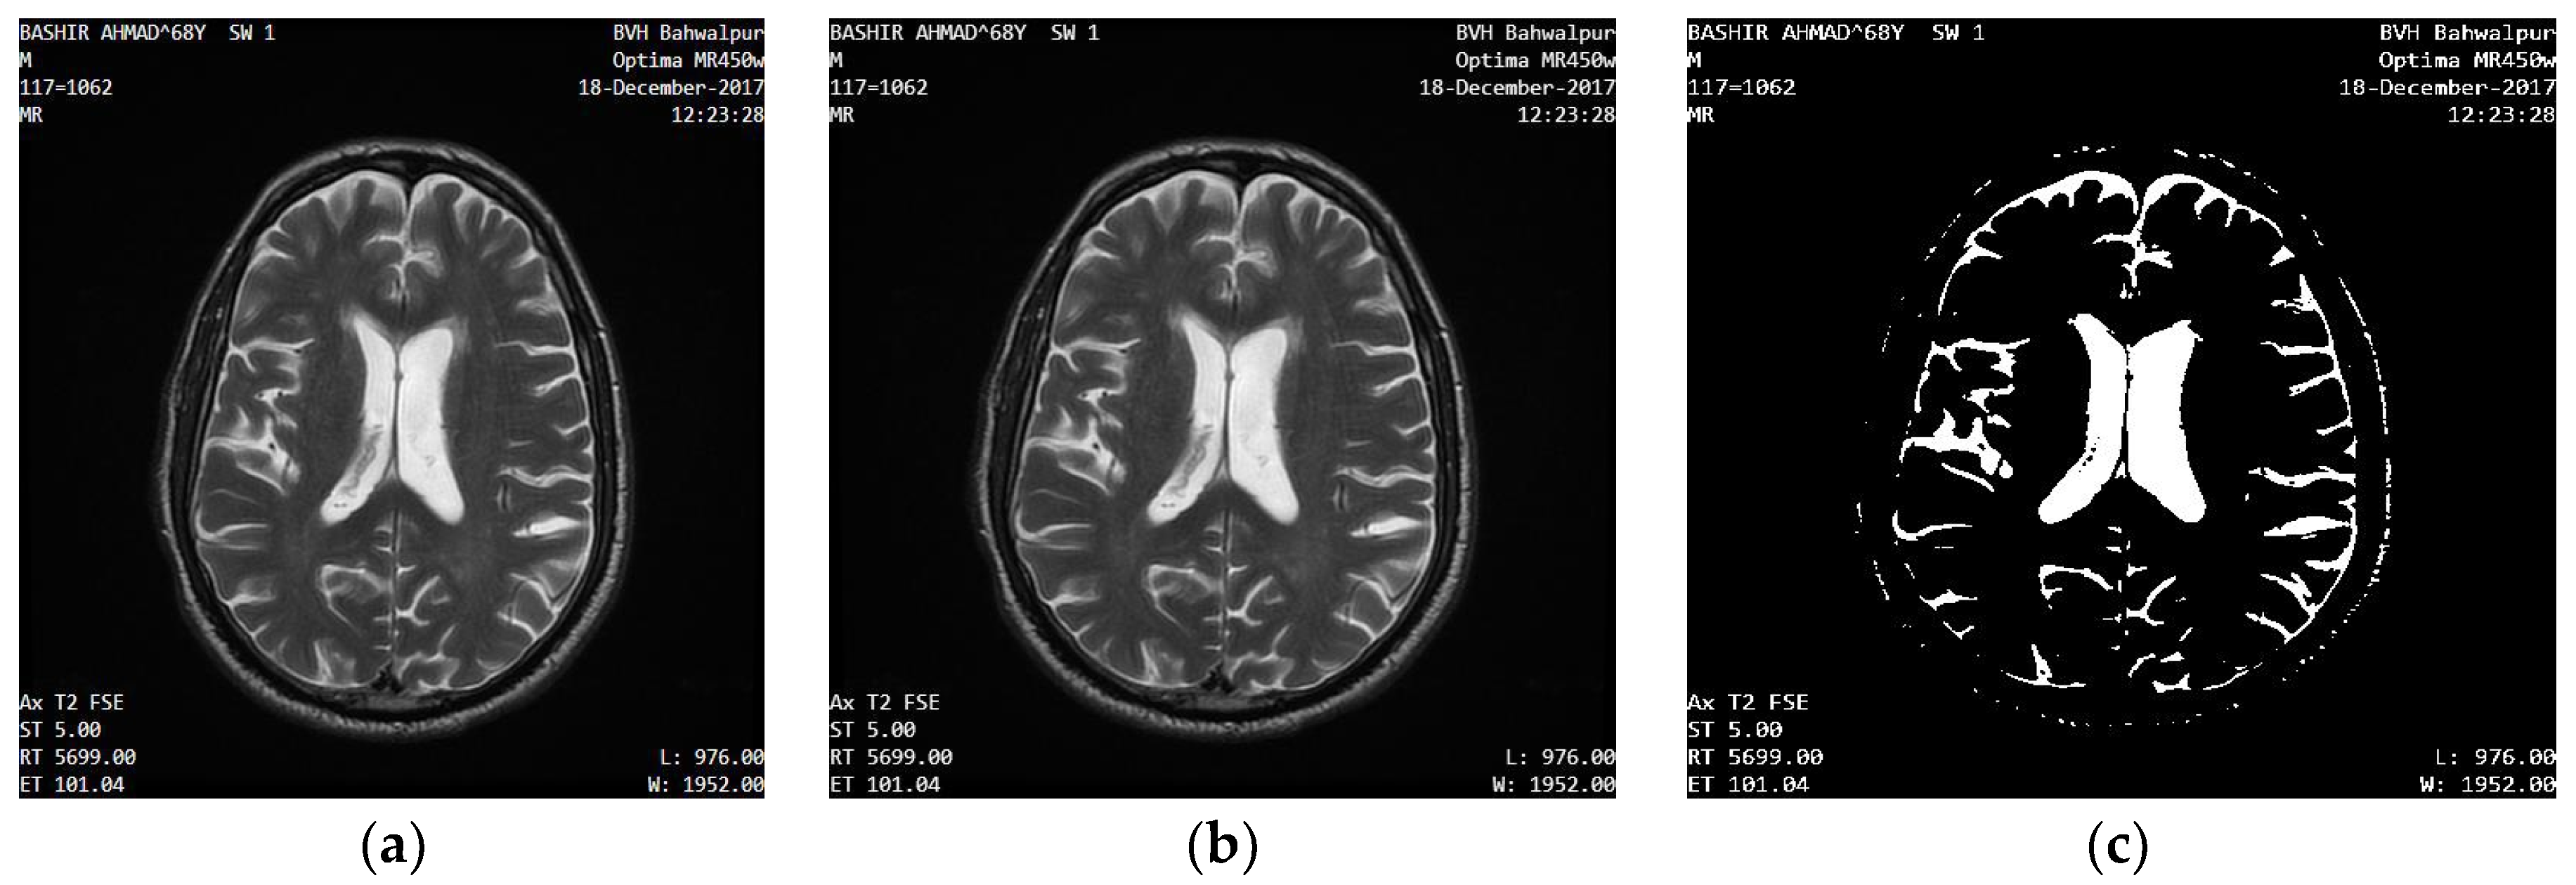

2.1. Brain Image Dataset

- BVH (Bahawal Victoria Hospital) brain MR images dataset;

- RIDER Neuro MRI imaging dataset.

2.2.1. Input Human Brain MR Images

2.2.2. Bitmap Conversion

2.2.3. Noise Removal